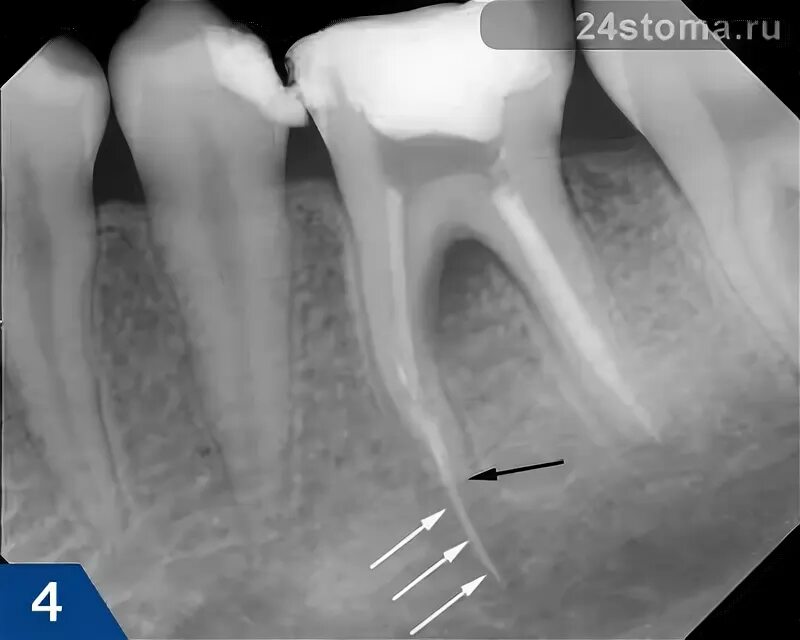

Пломбирование перфорации